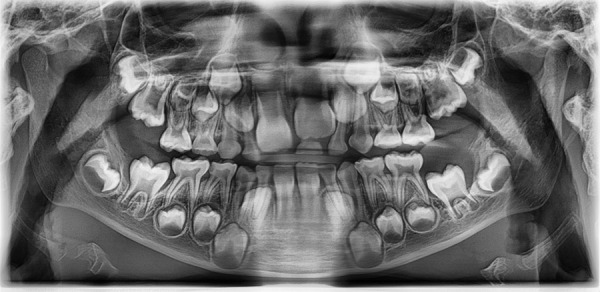

Dentigerous cysts are a common cystic pathology that develop between the first and third decade of life and are mainly associated with impacted or erupted mandibular third molars followed by maxillary canines and maxillary third molars. These kinds of cysts are the result of the proliferation of enamel epithelium after its formation, the pathogenesis of which is not clear. Few of these cysts have been reported in pediatric patients. The following case report presents the rare occurrence of a dentigerous cyst in a 6-year-old boy and describes the treatment administered.